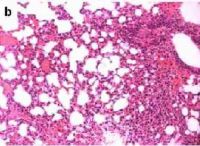

Postradiační změny v plicní tkáni

Postradiační změny v plicní tkáni.

Radiační pneumonitida je definována jako exsudativní zánět vznikající jako následek ionizujícího ozáření a je považována za alveolitis z poškození pneumocytů a endoteliálních buněk. Poškození se manifestuje obvykle za 4 - 6 měsíců po ozáření plic jednorázovou dávkou 8 Gy a vyšší. Jedná se o změny v ozářených oblastech a jsou tedy ohraničené. Radiační pneumonitida se klinicky projevuje pod obrazem nehnisavého exsudativního zánětu, tj. dušností, neproduktivním kašlem, teplotou a pleuritickou bolestí. Objektivně se u sledovaných pacientů zjišťuje přítomnost chrůpků a horečky. V případě dekompenzace nemoci se rozvíjí akutní respirační nedostatečnost nebo akutní cor pulmonale. Při histologickém vyšetření v manifestační fázi jsou popisovány intersticiální intraalveolární edém, zánětlivá infiltrace alveolů, zmnožení makrofágů a zvýšená buněčnost vazivové tkáně. Prognóza nemoci záleží především na léčbě, ale i při použití současných léčebných možností umírá asi čtvrtina až polovina všech nemocných.